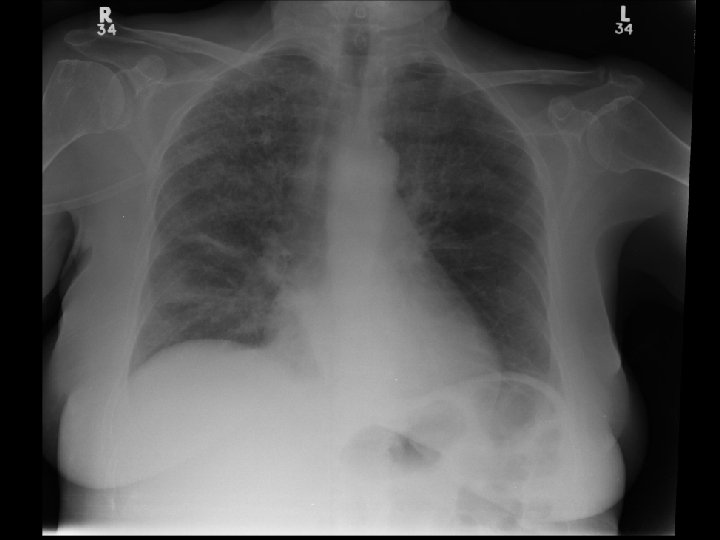

Case 1 (cont) • OE: w w HR 110 RR 24 BP 90/50 SPO 2 90% on 50%FM T 38. 5 CVS N hs; JVP 4 -5 cm ASA Chest: Fine crackles over bases, long expiratory time • Inv: w CBC: 98 11. 7 318 w Lytes 138 104 3. 5 26 w ABG: 7. 43 34 65 23 on Fi. O 2 0. 5

CT Angio Chest • No PE • Diffuse interstitial changes consistent with pulmonary edema • Left lower lobe opacity